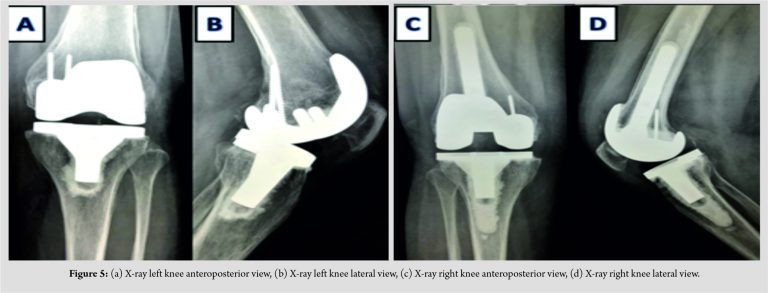

A cruciate retaining type of TKR was done (Fig. 5).

Posterior stabilized type of knee replacement component was used along with femoral extender stem (Fig. 5).Histopathological examination was done of the excised osteochondral fragments and tibial cuts. It revealed necrotic bone, surrounded by an area of fibrovascular granulation tissue on both the femoral and tibial sides (Fig. 7). Patient was mobilized full weight bearing after surgery and has good functional outcome at 2 years follow-up.